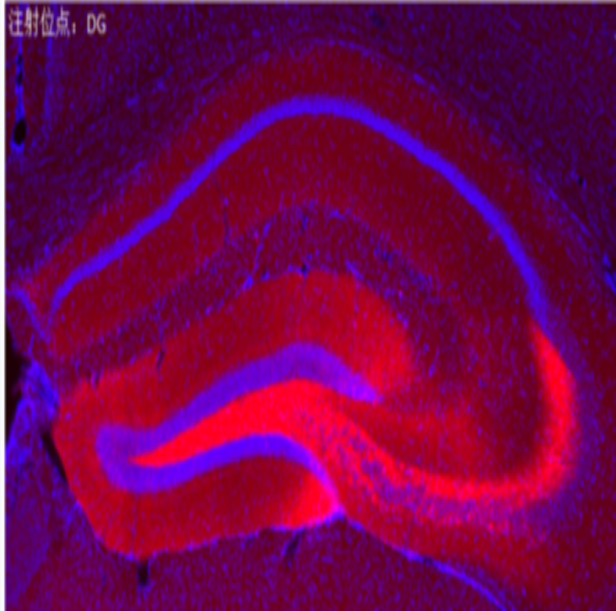

rAAV-CaMKIIα-hChR2(E123T/T159C)-mCherry

CaMKIIα:Ca2+/calmodulin-dependent protein kinase II,兴奋性神经元启动子。

ChR2: 是Channelrhodopsin 的一种,属于视紫质蛋白(rhodopsins),是一类光控的离子通道。ChR2 对470nm 蓝光吸收最明显,在蓝光照射下,可使Na+等阳离子内流,激活神经元。

hChR2(E123T/T159C):是基于ChR2 的高频工具,或者称为ChETATC,在Karl Deisseroth 实验室被称为ChETA 的升级版之一。通过引进T159C 的点突变,显著改进了ChETA 内向电流弱的短板,平台期内向电流接近hChR2(H134R),同时还保持了ChETA 分子关闭迅速的特点,从而使该通道具有优异的性质。在E123T 突变的基础上,T159C 对内向电流的增加效果显著好于H134R。

mCherry:红色荧光蛋白,激发波长587nm,发射波长610nm。